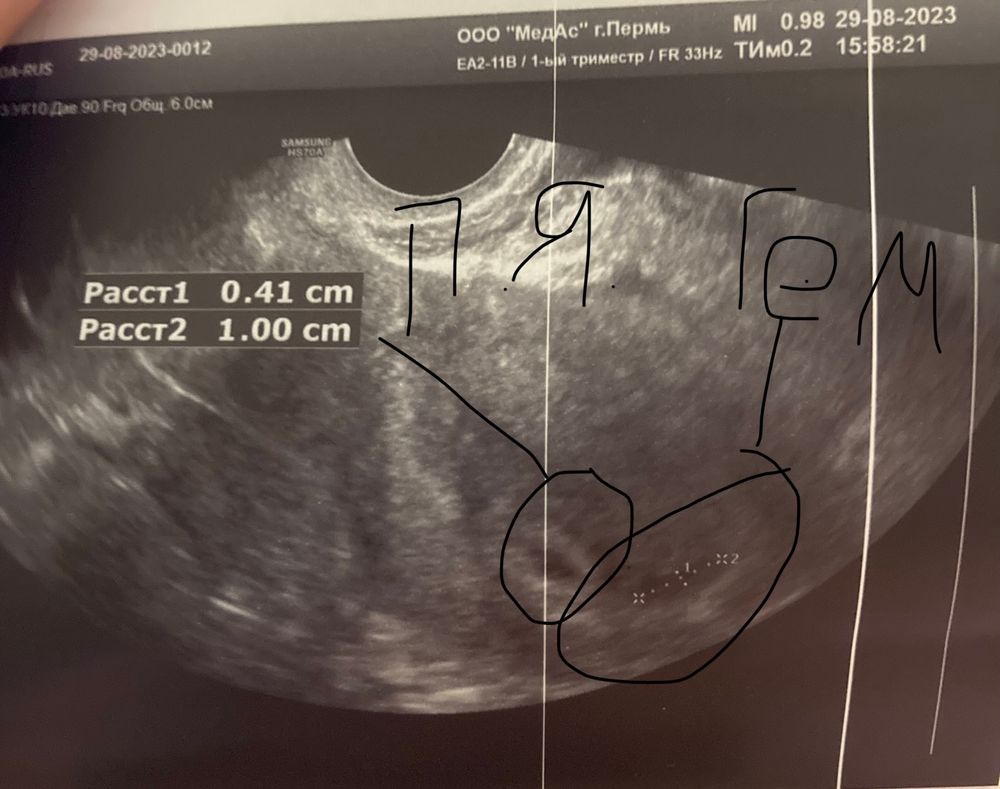

19дпп ретрохориальная гематома

Утром началась светло-коричневая мазня. Ре сказала пить транескам и дюфастон сразу 4 штуки. Не выдержала, поехала на узи. Узист сказал что вот гематома есть, лежать или ходить разницы нет, типа ни на что не влияет 🤷♀️ выпила транескам 1000, вроде больше не мажет. Завтра плановое узи у ре, ей не скажу, что ездила, подумает еще что истеричка) пусть лучше еще раз посмотрят. В остальном вроде все нормально, но только смутило врача желтое тело -12 мм. Девочки, у кого было? Чем закончилось? Беременность получается 5 нед и 3 дня (акушерский срок). Плодное яйцо 0,5 см